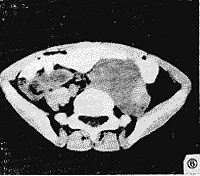

参照手术所见,将肿块分为囊实混合性,囊性和实质性三类:①囊性:CT平扫为均匀低密度灶,囊内无增强,包膜及分隔可轻至中度强化(CT值升高10~40 Hu),此类肿瘤共7例,3例为囊性淋巴管瘤,CT值<16 Hu,3例为成熟型囊性畸胎瘤,CT值>20 Hu(图1),另一例为巨大分化良好型平滑肌肉瘤,其内可见多个房隔强化,囊内CT值26~42 Hu(图2)。②囊实混合性:特点为大囊性病灶加一部分实质,囊性部分CT值较高,15~27 Hu,实质部分20~42 Hu(图3),此类共计2例,均为间叶组织恶性肿瘤。③实质性:共计22例,又可分为不均匀和均匀性。不均匀实性,标本切面上见肿块内有多发灶性液化,坏死或小囊变及多发出血。此类最多见,计21例,CT表现为不均匀性团块,密度不均,见片状不规则低密度灶,增强后见不均匀性强化(图4及图6),此类肿瘤良、恶性均较多见,其中脂肪肉瘤5例,平滑肌肉瘤6例,神经源性肿瘤3例及分类不明者2例,血管内皮肉瘤1例。均匀实质性肿瘤1例,为平滑肌瘤。此外,在血管内皮肉瘤及神经节细胞瘤、畸胎瘤中可见散在斑点状,结节状钙化。

图6 CT示脊柱前缘左髂腰肌内侧境界清晰肿块,左髂动脉向右移位,左腰大肌向前外方移位,腹腔内肠管向前移位。手术病理:神经节细胞瘤

3.1 腹膜后肿瘤的定位诊断

CT具有较高的密度及空间分辨力,较客观地显示肿块位置,大小及毗邻关系,还可借助增强扫描进一步了解病变内部及周围情况,本组腹膜后肿瘤CT检出率达100 %,定位正确率达94 %,较小的肿瘤CT定位较易,肿瘤大时定位常较困难[1,2],由于CT固有横断扫描方式,尤其是相邻器官受压萎缩时,脂肪间隔不易显示,易将原发腹膜后肿瘤误诊为肝、胰或肾上腺肿瘤,本组中,由于肿块较小,有1例腹膜后成熟型囊性畸胎瘤误诊为肾上腺肿瘤(图1),1例腹膜后血管内皮肉瘤误诊为肝癌(图4),但由于螺旋CT的出现,可通过多平面重建克服这一缺陷。